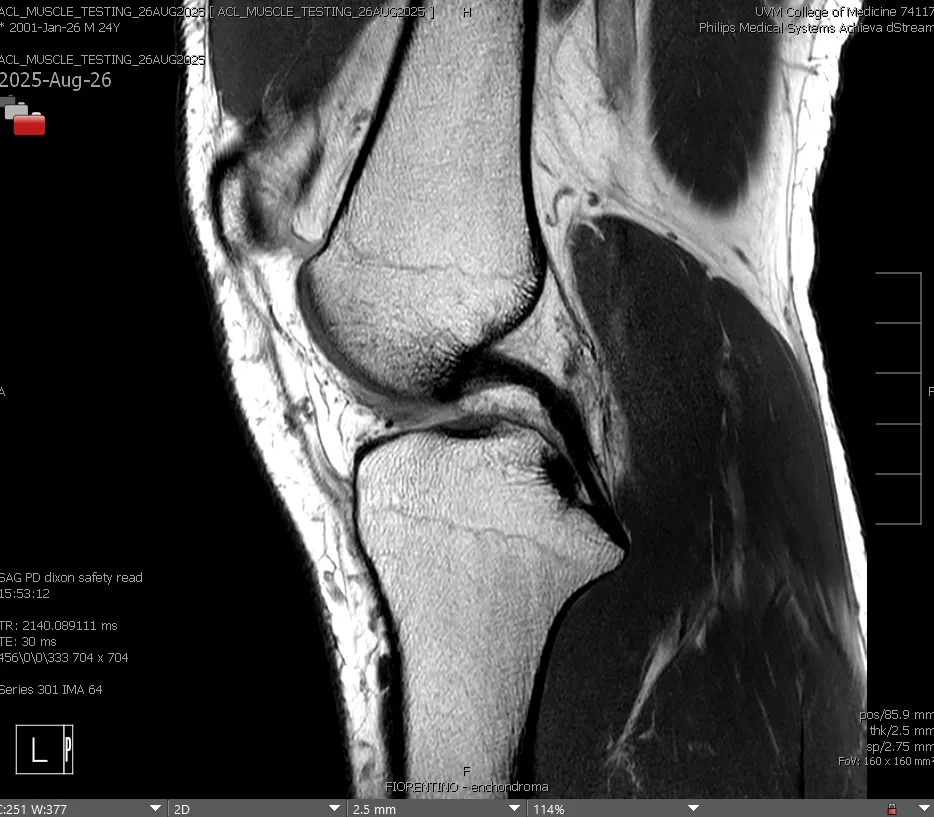

Below are image examples from several types of MRI equipment that researchers may use.

Orthopedic Images

Dr Beynnon - PTOA study